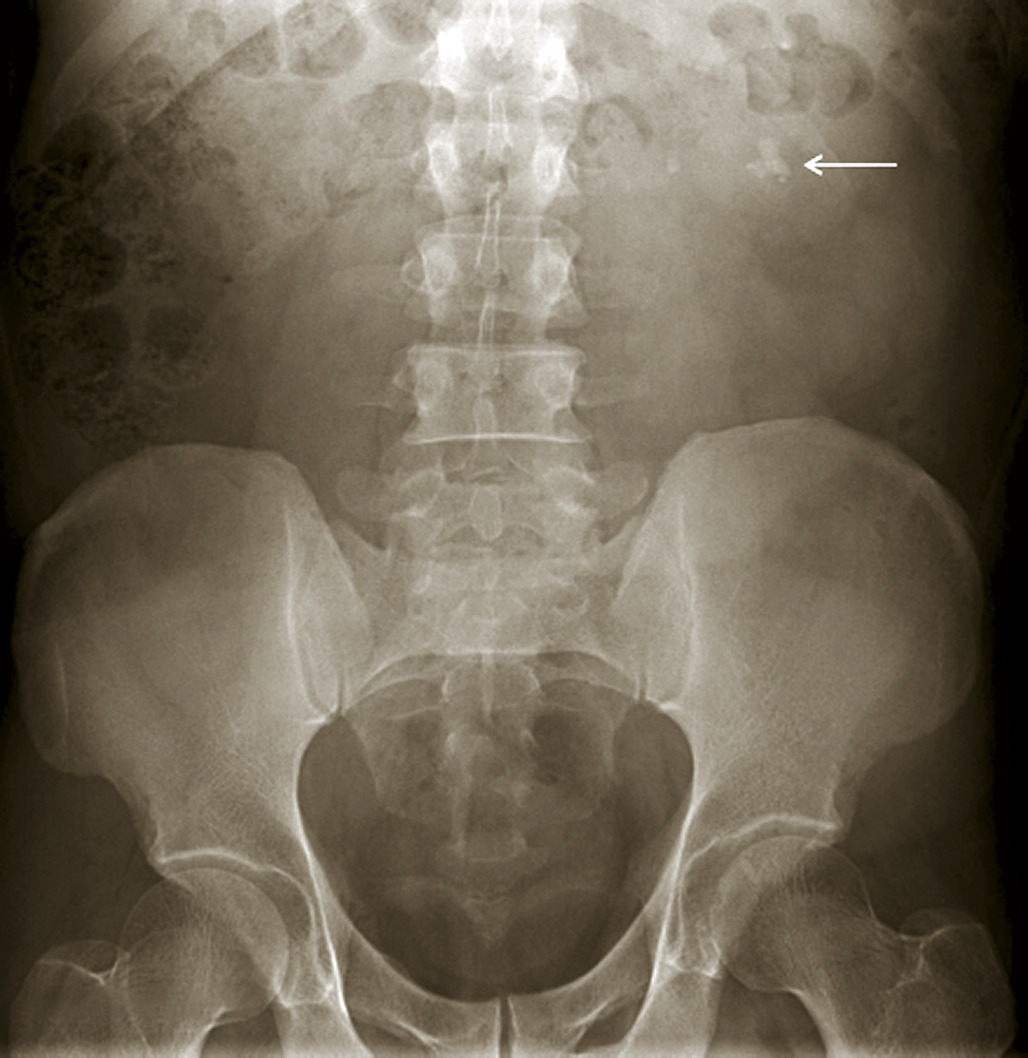

Les clichés d’abdomen sans préparation (ASP) ne sont plus indiqués dans les douleurs abdominales aiguës inexpliquées ou justifiant une hospitalisation (suspicion d’urgence chirurgicale), ou en cas de fièvre associée (suspicion d’abcès abdominal), ou de suspicion de perforation, d’appendicite ou de diverticulite sigmoïdienne. Dans ces cas, l’examen de choix est le scanner abdomino-pelvien et, suivant les cas, l’échographie abdomino-pelvienne ou l’IRM abdomino-pelvienne chez la femme enceinte. Les clichés d’ASP restent indiqués : en cas de constipation chez la personne âgée ou en milieu psychiatrique (en l’absence de technique alternative d’imagerie), ou de suspicion de colectasie au cours d’une maladie inflammatoire chronique de l’intestin (MICI), ou en deuxième intention au cours d’une pyélo­néphrite après visualisation d’une dilatation des cavités pyélo­calicielles à l’échographie (fig. 5), ou en cas d’ingestion de corps étranger. L’ASP ne doit pas retarder la réalisation d’examens d’imagerie plus utiles au diagnostic étiologique.

L’échographie peut montrer une discrète asymétrie des cavités excrétrices rénales, voire l’obstacle lithiasique avec dilatation d’amont (fig. 2 et 3). L’uroscanner complète le bilan et localise si besoin le calcul. Outre le traitement de la cause (calcul, compression extrinsèque…), le traitement antalgique est primordial : anti-inflammatoires non stéroïdiens (AINS), paracétamol, anti­spasmodiques voire dérivés morphiniques. On procédera à la pose d’une sonde urétérale en cas d’anurie (rein unique), de fièvre sur rétention du haut appareil ou de crise hyperalgique.